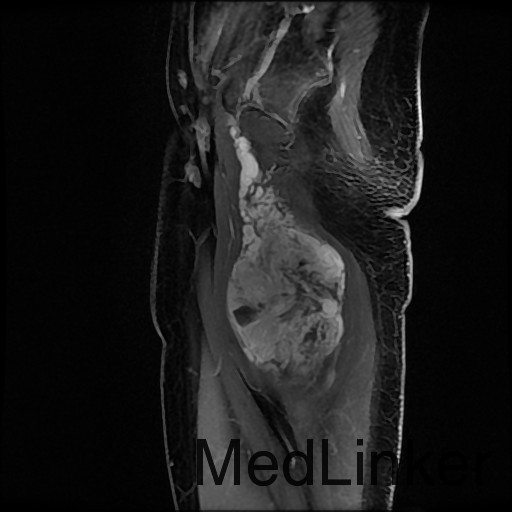

诊断:肺占位性病变(转移瘤?);大腿软组织疾患(右侧大腿肿物) 治疗:入院右下肢MR平扫+增强扫描:右侧大收肌软组织占位性病变,考虑间叶源性恶性肿瘤可能性大,血管源性可能?瘤周多发静脉曲张及侧枝循环形成,建议CT增强扫描进一步检查明确血管情况。遂于声引导下右大腿肿物穿刺活检,病理结果提示:(右大腿肿物)送检穿刺组织,肿瘤细胞形成器官样及腺泡状结构,细胞巢间为纤维性分隔,细胞呈大圆形、多边形,胞质丰富透亮,部分呈嗜伊红色,细胞核大,核分裂象少见,结合临床病史及免疫组化,考虑为腺泡状软组织肉瘤。免疫组化结果(①):CK(-),Vim(-),Ki-67(5%+),HMB45(-),MelanA(-),SMA(+),desmin(-),Myogenin(-),MyoD1(-),S100(-),NSE(部分+),CD56(-)。